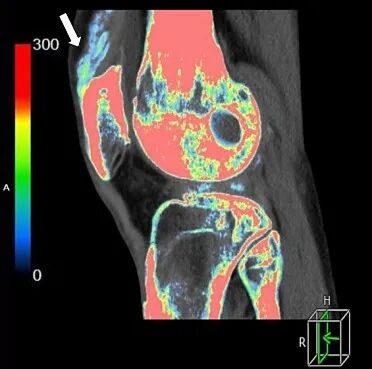

与X线平片及单能量CT相比,双能量能谱CT能够超早期显示更细小的尿酸盐结晶的存在;与MRI相比,双能量能谱CT可以进行多关节的扫描成像,不仅能够直观分析检查部位是否有尿酸盐结晶存在, 并且可以分析其数量、大小、形态、位置、分布以及临近关节骨质及软组织损害的情况。

腕关节尿酸盐(痛风石)沉积